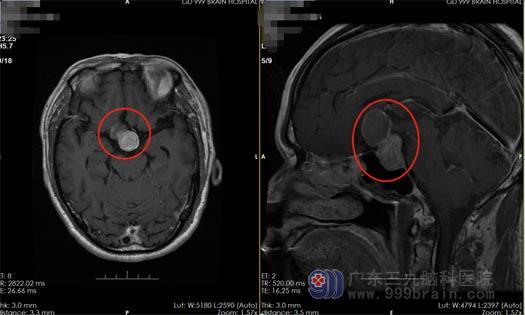

经过进一步的头部MR检查,发现患者“颅内垂体窝处的肿瘤压迫视交叉、视神经”,诊断为垂体瘤。医生分析:吴先生之前就有视力下降,所以垂体功能减退没有引起足够的注意和重视,近期颅内肿瘤增大,进一步压迫视交叉、视神经,才导致了症状的加重。

吴先生及家人充分了解病情后,同意手术治疗。神经外五科手术团队为吴先生行“内镜经鼻蝶鞍区占位切除术+颅低重建术”,术中发现肿瘤大小约为27mm×21mm×41mm,严重压迫视交叉、视神经,并且周边血供丰富,为手术带来了极大的困难;在手术医生的密切配合下,凭借着丰富的手术经验和先进的仪器设备,将手术顺利完成,术中出血量少,在全切肿瘤的同时保留了垂体功能。术后,吴先生的病情得到了很大改善,视力也开始逐渐恢复。

▲术前